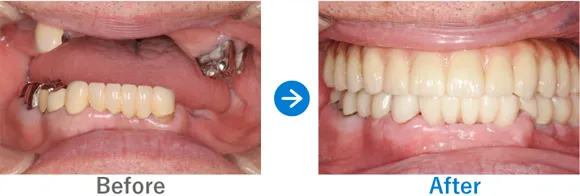

ほとんどの歯が残存していないケース

Case1

歯が1本もない状態からインプラント治療で噛める幸せを取り戻された方

歯が1本もない状態、10年以上前から上下総義歯(総入れ歯)

上顎ALLON6、下顎ALLON4、

リオペ上顎追加埋入ザイゴマインプラント2本

9,823,000円(上顎6,248,000円、下顎3,575,000円/内訳:上顎オールオン6(ノーベルザイゴマインプラント2本・ストローマンインプラント4本)、下顎オールオン4(ストローマンインプラント4本)3Dモデルガイド*、仮歯、セデーション、ボツリヌストキシン注射、3D模型、保証10年)

*単体のインプラントのガイドとは異なる、オールオン4専用のガイド

※当時の価格で現在とは異なる場合があります。

来院の背景

10年以上前から上下義歯(総入れ歯)だが、義歯が痛くて、食事に困っている。他院にて仮義歯を作ってもらっていたが担当医が辞めたこともあり、インプラントを検討。ネットで探して退院。痛みなく食事がしたい。

治療結果

上下ALLON4、右上5、左上3、リオペザイゴマインプラント2本追加順調の経過、治療終了、メンテナンス来院。インプラントで噛めるようになり、喜んでいただいた。しっかりセルフケアを頑張っておられます。お顔の表情も明るくなられて、気持ちも前向きに過ごされています。